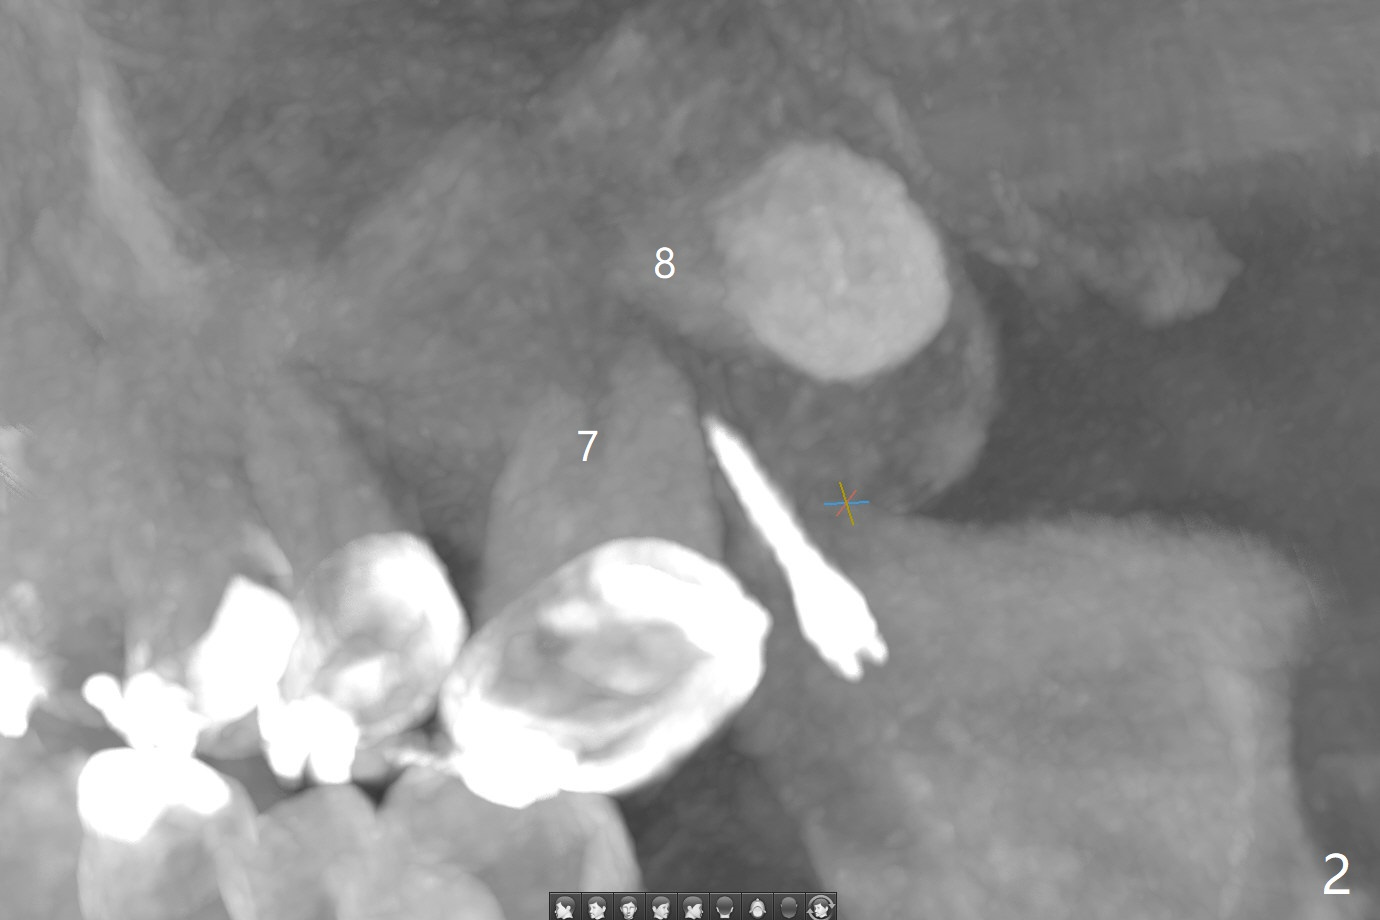

为了在左上6,左下7种植,使用右上3至左上5作为支抗推左上7远中,但是六个月效果不显著(图一),CT显示阻生牙(图一,二:8)没有阻挡。7远中植入1.6x8毫米微型植体,不过接近7根尖(图三),微型植体应该改变角度,而且往远中颊侧移位。最后效果不错(图四),植体马上启用(图五),而且同时取模做左下7导板。在微型植体牵引下,左上7的确往远中移位(图六,与图四对比),但是植体松动,马上植入3x10(2)毫米一段式植体,由于8阻挡,后者没有完全就位,稳定性差,没有启动。几天后也脱落。病人急着完成治疗,因为咀嚼困难。补救方法便是拔除阻生牙9(图七:x),让植体完全就位。切开后发现牙槽嵴处严重骨质吸收缺损(图八:D),离7很近,不适合种植。拔除8后(图九:S(socket)),两处植骨(粘性,图十),覆盖PRF膜,缝合。矫正九个月6空间相当双尖牙(图十二),还想增加2毫米才种植,病人急于完成治疗,所以再次植入微型植体,不同之处是切开,发现7远中颊侧骨质密度低(用探针),因此微型植体在腭侧植入(图十一:P),扭力似乎高,1.6x8毫米植体仿佛植入8牙槽窝(图十二:红虚线)。微型植体牵引一个月,磨牙缺牙间隙大约前磨牙大小,准备在远中(图十三)植入直径小植体(图十四),当后者整合时,用它继续推7。